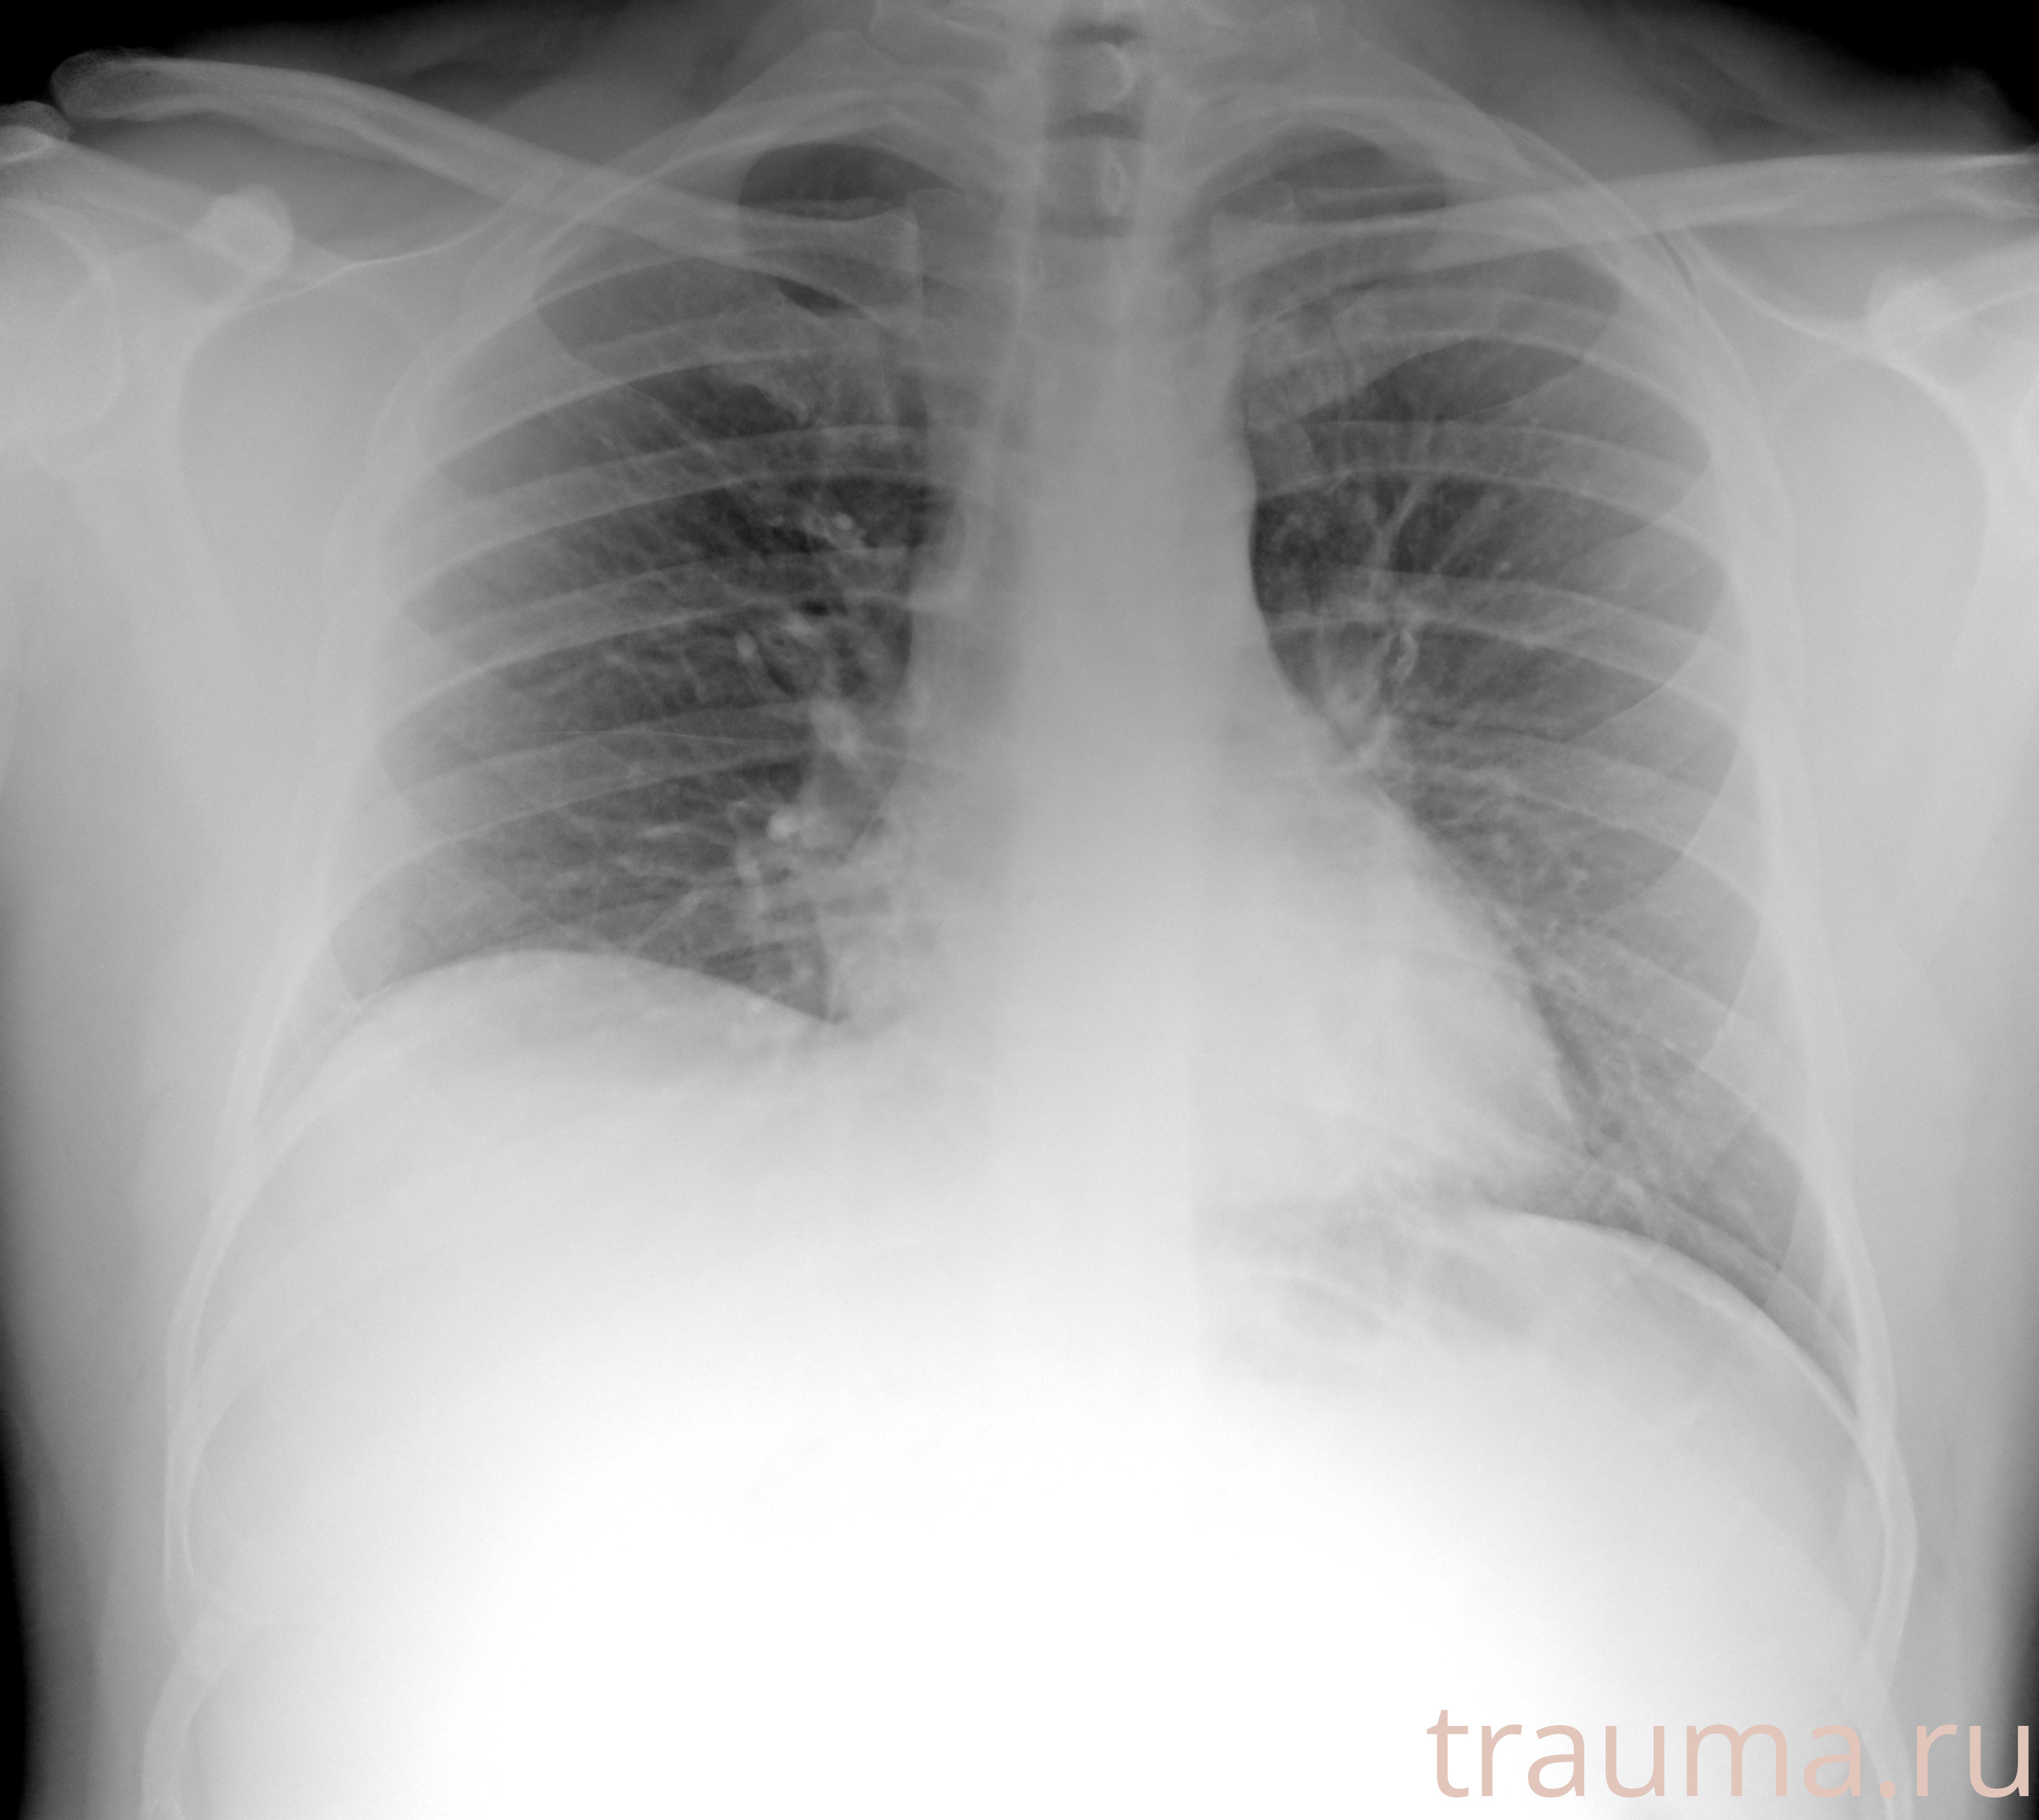

Рентгенограммы

Рентген на дому: по вашему адресу приезжает врач-рентгенолог, травматолог-ортопед с мобильным рентгеновским аппаратом, проводит диагностику травмы или заболевания, делает необходимые рентгенограммы, дает рекомендации по дальнейшему лечению. Получить качественные снимки в домашних условиях возможно благодаря уникальной методике, разработанной МосРентген Центром для института  Склифосовского

Яркость: 1   Контраст: 1   Инвертировать: 0 Увеличение: 1

Перетаскивайте мышь вверх/вниз для контраста, влево/право для яркости. Прокрутка колесом изменяет масштаб. Нажмите Сбросить для возврата к исходному изображению. При увеличении держите мышь в той области, которую хотите рассмотреть.